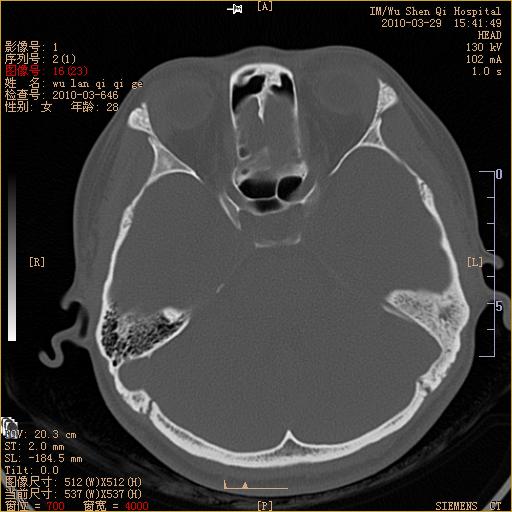

标题: CT25398:女,左耳流脓两年余,带有异物 [打印本页]

标题: CT25398:女,左耳流脓两年余,带有异物

左侧中耳乳突炎,不排除胆脂瘤形成。

左侧中耳乳突炎,胆脂瘤形成。

1)左侧慢性中耳乳突炎并肉芽肿(或胆脂瘤)形成。2)考虑左侧颞骨慢性炎症伴骨质增生硬化,不排除骨纤。